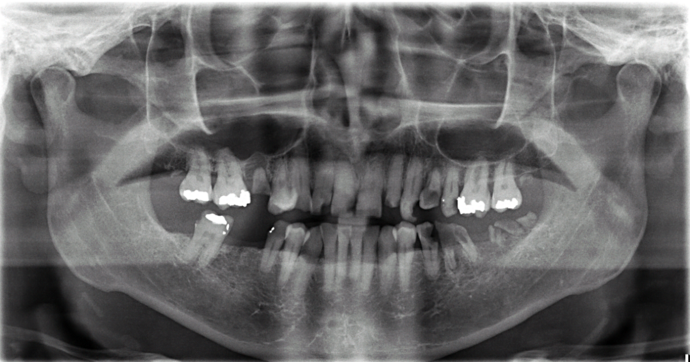

All-on-4/ Full Mouth Dental Implants / Teeth in a Day: Case 16-Upper and Lower All-on-4 Bridges

Patient had severe cavities throughout the mouth due to extreme dry mouth and history of use of tobacco. Patient was very discouraged as he had hated the idea of wearing dentures. Patient found Dr Bidra online and sought treatment and had all his teeth extracted and implants placed and new teeth installed all in 1 day! Patient was extremely satisfied with his transformation and eradication of all disease and bacterial infections.

Procedures : extractions, implants, All on 4 , Teeth in a day, no bone grafting and full mouth reconstruction with monolithic zirconia bridges.